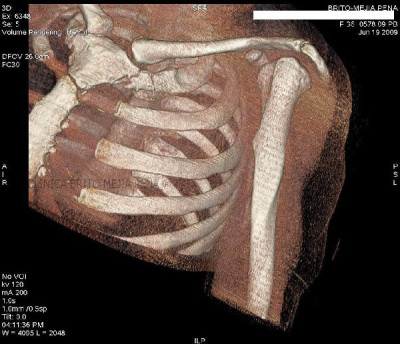

Fracturas costales